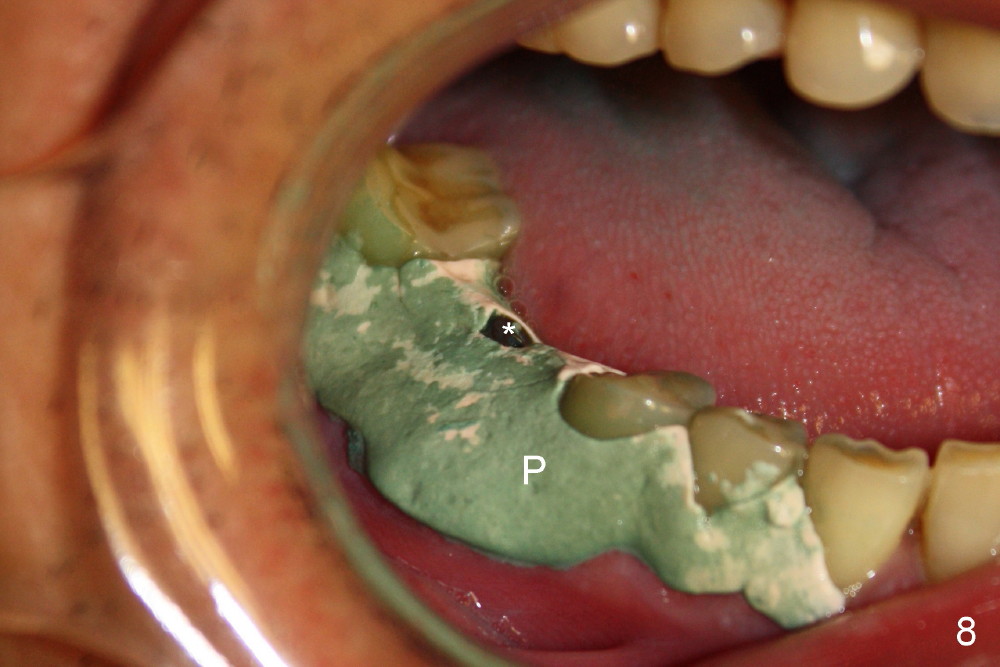

As to where to place an implant, we try to engage the largest tap (8 mm in diameter) into the mesial socket without binding. The buccal plate of the mesial socket is missing. It is risky to extend osteotomy in the mesial socket. Besides, the septum (Fig. 4 S) is not as tall as the distal socket (D). It appears that the distal socket is the safest place to place an implant. Furthermore, no drill is used for distal osteotomy. Instead two osteotomes (3.5x15 and 4x15 mm tapered osteotomes) are used to expand the distal socket with intention to push the septum mesially. Since the bone density is high, the osteotomes seem not to work as effectively as expected. Then a 4.5x17 mm tap is placed at the depth ~ 14 mm with stability (Fig.5). Finally a 5x14 mm tissue-level implant is placed with insertion torque >60 Ncm (Fig.6). Allograft is placed in the mesial socket and buccal aspect of the distal socket, followed by insertion of collagen plug and membrane (Fig.7). After insertion of an abutment (Fig.8 (taken 6 days postop) *), perio dressing (P) is applied to cover the wound. There is no postop paresthesia.